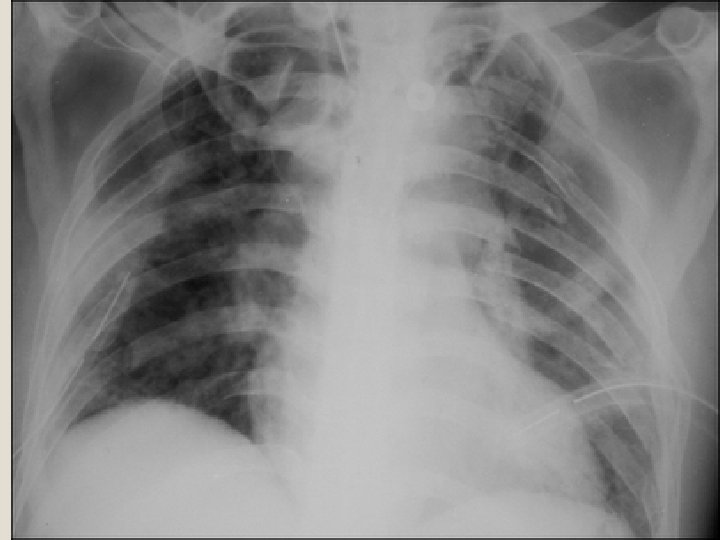

�Dengan foto toraks akan lebih jelas karena akan terlihat fraktur iga yang multipel, akan tetapi terpisahnya sendi costochondral tidak akan terlihat. �Pemeriksaan analisis gas darah yaitu adanya hipoksia akibat kegagalan pernafasan, juga membantu dalam diagnosis Flail Chest.